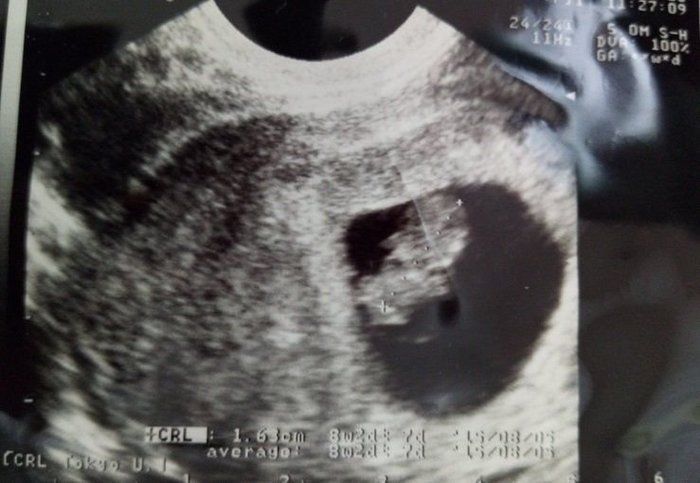

水野谷つむぎさんの妊娠8週のエコー写真 少しずつ大きくなっている赤ちゃん

赤ちゃんの大きさは1.5㎝くらい。この頃、つわりらしきものを感じ始めました。食の好みが変わることはありませんでしたが、量が食べられなくなり、とても疲れやすく、帰宅後ご飯を食べたら力尽き、午前3時ごろにやっと起きて、洗い物をするような日々でした。

そんな頃に病院から突然の電話があり、なんと病院が閉院することを聞かされました。そして、「もう妊娠3カ月に入るので、急いで別に出産する病院を探して下さい」と言われました。妊娠3カ月になったら入院予約、前金入金の病院が多いための指示でした。あまりのことに、電話を切った後、呆然と立ち尽くしましてしまいました。